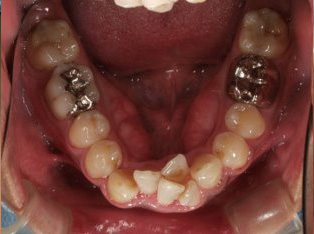

治療前

治療終了前